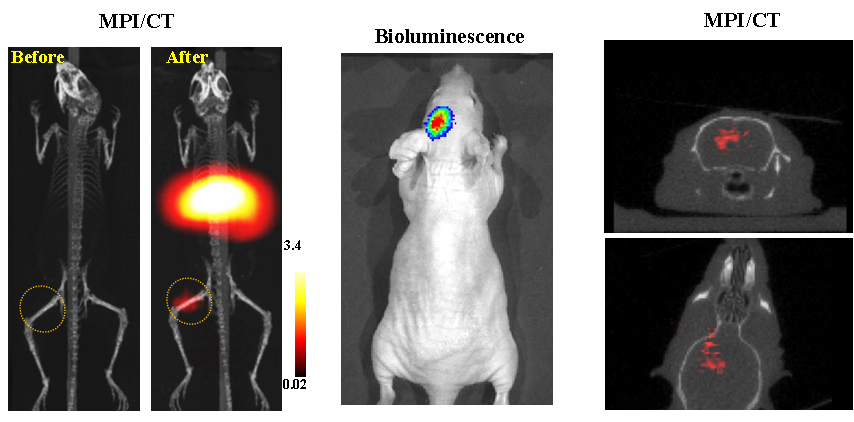

今年二月份,宋国胜教授与斯坦福大学饶江宏教授合作,通过系统的研究获得了影响磁性粒子成像信号的作用规律和关键原理,开发了新型磁性粒子探针---FeCo合金粒子,并首次应用于磁性粒子成像(MPI)。该造影剂在极低含量时(5 ng)仍具有很强的造影效果。这意味着,未来在进行人体成像时,可以使用更小剂量的造影剂,从而避免高剂量造影剂引起的肾肝损伤。基于MPI的直接成像原理,我们可以对造影剂进行正相和无背景干扰的活体成像,极大地提高信噪比。这项技术为肿瘤早期诊断、癌细胞示踪、脑中风、药物输送治疗、肺部灌注成像、胃肠出血、神经退行性疾病、磁热治疗等在活体中的可视化研究,提供了强有力的手段。相关研究成果以经典三级

为第一单位发表在Nature 子刊《Nature Biomedical Engineering》。该期刊是“生物医学工程”的顶级期刊。宋国胜教授为该论文的共同通讯作者。